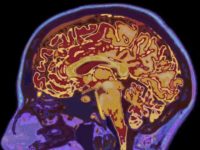

More Research On Building Better Brains Through Participating In The Arts

"Children that are playing music, their brain structure actually changes and their cerebral cortex actually gets larger." - NPR